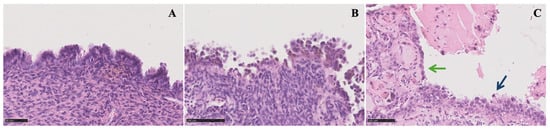

Endometrioma is predominantly a unilocular cyst displaying a uniform “ground-glass” echogenicity without observable solid or vascularized papillary components, facilitating its diagnosing in non-experienced hands (Figure 2).

Figure 2.

Ultrasound images of (a) a typical endometrioma, (b) an atypical endometrioma, (c) a clear cell carcinoma, and (d) an endometrioid carcinoma. The ultrasonographic diagnosis was confirmed by pathological examination, and patients provided informed consent for the use of their images.

However, endometrioma can be defined as atypical when at least one of the following sonographic characteristics is observed: cyst diameters of 10 ± 1 cm, multi-cystic formations, the presence of any solid component or papillary structure—defined by IOTA as a protrusion of solid tissue into a cyst cavity with a minimum height of 3 mm—and the detection of blood flow at any level [56,57]. The IOTA risk score considers unilocular cysts with small solid components (less than 7 mm of maximum diameters), acoustic shadows, uniform multilocular tumors with maximum diameters less than 10 cm, and the absence of blood flow as benign features. Malignant features encompass irregular solid tumors, ascites, four or more papillary structures, irregular multilocular solid tumors with a maximum diameter ≥10 cm, and strong blood flow. Typically, obtaining a histological evaluation post intervention for atypical endometriomas deemed at neoplastic risk is recommended. However, additional considerations, including patient’s age or fertility desires, are essential for determining the most appropriate management approach [56,58].

Ovarian CCC is typically diagnosed in its early stages, presenting as a sizable unilateral mass with solid components. Patients with CCC arising from endometriosis tend to be younger compared to those with non-endometriosis-associated clear cell carcinoma. Moreover, CCC originating from endometriosis may frequently display a ground-glass echogenicity in the cyst fluid [59].

EnOCs typically present as larger, unilateral, multilocular-solid, or solid tumors. The ultrasound features of EnOC originating from endometriosis exhibit distinctions from those not associated with endometriosis [52].

Borderline tumors and carcinomas originating from endometriomas typically show a vascularized solid component. An age of 45 years or older and endometrioma size of 8 cm or more are significant factors that independently predict the development of ovarian cancer in women with endometriomas [10,22,31].